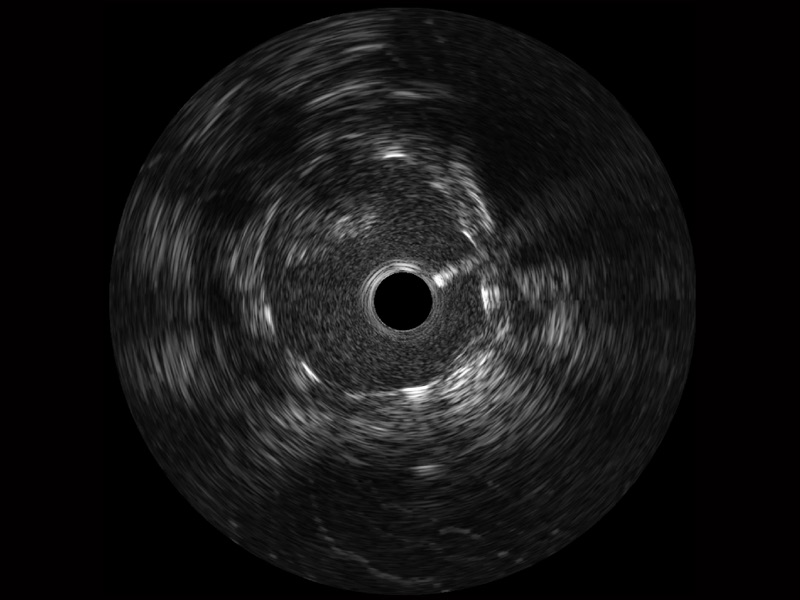

乐玩lewin国际宽频IVUS图像

对比传统IVUS导管成像,乐玩lewin国际宽频IVUS图像的近场支架梁显影更细腻,远场中膜外血管仍清晰可辨,兼顾远中近,兼顾分辨力与穿透深度